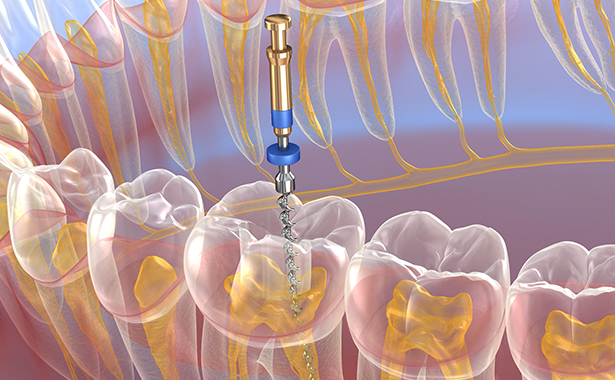

Latest Technology

We use the latest digital and diagnostic tools in our state of the art surgeries to give you fantastic results.

Root Canal Treatment